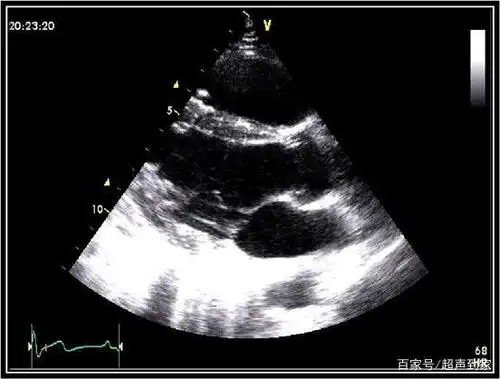

心脏彩超 12个常用切面图像及标注

心脏的胸骨旁长轴切面(b型)

超声心动图常用切面的打法图解